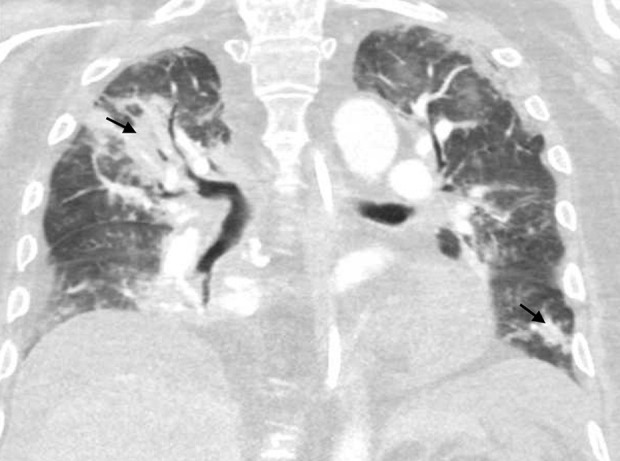

BACKGROUND Adenoviruses are double-stranded DNA viruses capable of causing a spectrum of diseases from mild respiratory infections to severe systemic illnesses. Disseminated adenovirus is evidenced by gastrointestinal, pulmonary, genitourinary, neurologic and even cardiac involvement. In immunocompromised individuals, adenovirus infections can become severe and are often associated with significant morbidity and mortality. CASE REPORT A 52-year-old man with a history of large granular lymphocytic (LGL) leukemia underwent haploidentical hematopoietic stem cell transplantation (HSCT). His course was complicated by the diagnosis of hemorrhagic cystitis with findings of adenovirus. His condition rapidly declined, necessitating Intensive Care Unit (ICU) admission. Comprehensive workup identified adenovirus in the serum and cerebrospinal fluid (CSF), bronchoalveolar lavage fluid, and positive stool adenovirus. Echocardiographic evaluation revealed a moderate pericardial effusion requiring pericardiocentesis. Unfortunately, adenovirus testing of the aspirate could not be performed. Given the diagnosis of disseminated adenovirus infection, treatment with cidofovir and probenecid was initiated, but despite these interventions, the patient's status continued to deteriorate complicated by multiorgan failure and refractory shock. CONCLUSIONS This case underscores the complexity of diagnosing disseminated adenovirus, particularly given the potential for multiorgan system involvement. Early recognition is essential, such as viral polymerase chain reaction (PCR), playing a critical role in the identification and monitoring of infection. The case further emphasizes the pressing need for continued research into novel antiviral therapies and preventive measures to mitigate the risk of adenovirus in this vulnerable population.